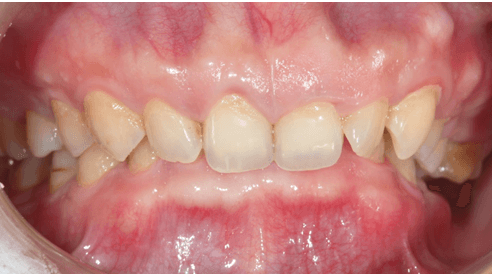

Răng cụp là một tình trạng sai lệch khớp cắn cần được điều chỉnh bằng phương pháp chỉnh nha. Tuy nhiên, đôi khi tình trạng này lại xuất hiện như một biến chứng của quá trình chỉnh nha.

Răng cụp có đặc điểm chính là răng mọc nghiêng vào trong, không đặt đúng trục so với các răng xung quanh. Điều này khiến cho chân răng không nằm hoàn toàn trong xương, gây ra nhiều vấn đề về chức năng và thẩm mỹ của răng miệng.

Các đặc điểm của răng cụp bao gồm: